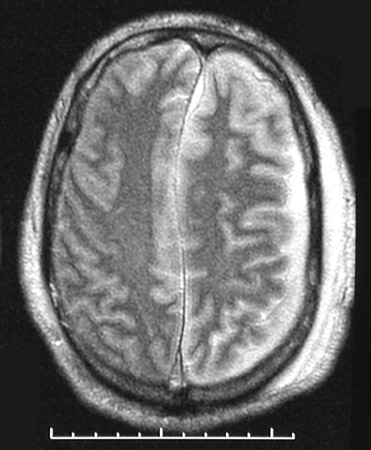

| The T2 weighted MRI scans in axial view above and below show bright fluid in the subdural region on the left, representing a subdural empyema. Note also the effacement of the left ventricle with midline shift due to the brain swelling from the inflammation. This may represent hematogenous spread of infection, or a prior subdural hematoma may become infected. Both events are not common. |